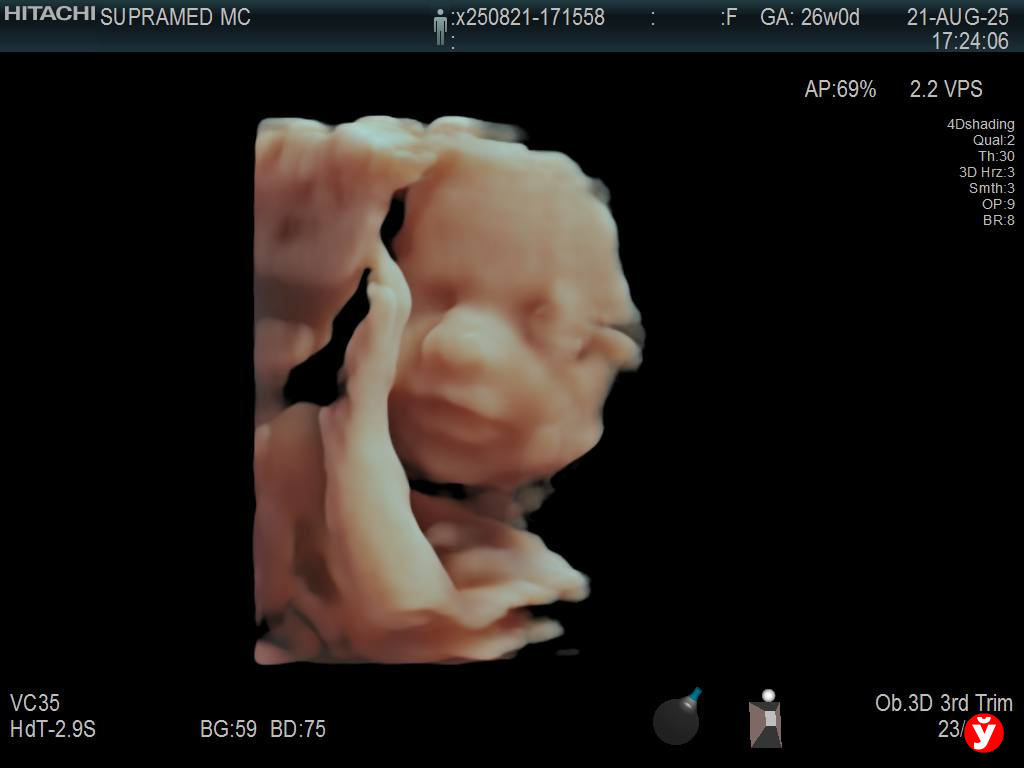

Первый скрининг прошёл в напряжении, а вот 3D-УЗИ заставило мой мир остановиться на мгновение. На экране — мальчик, он зевает, вытягивает ножки, играет с пуповиной.

С первым ребёнком я видела на УЗИ только развитие, со вторым — уже улыбку, а с третьим — даже черты лица.

Это невероятное ощущение, как будто получаешь знак: всё будет хорошо.